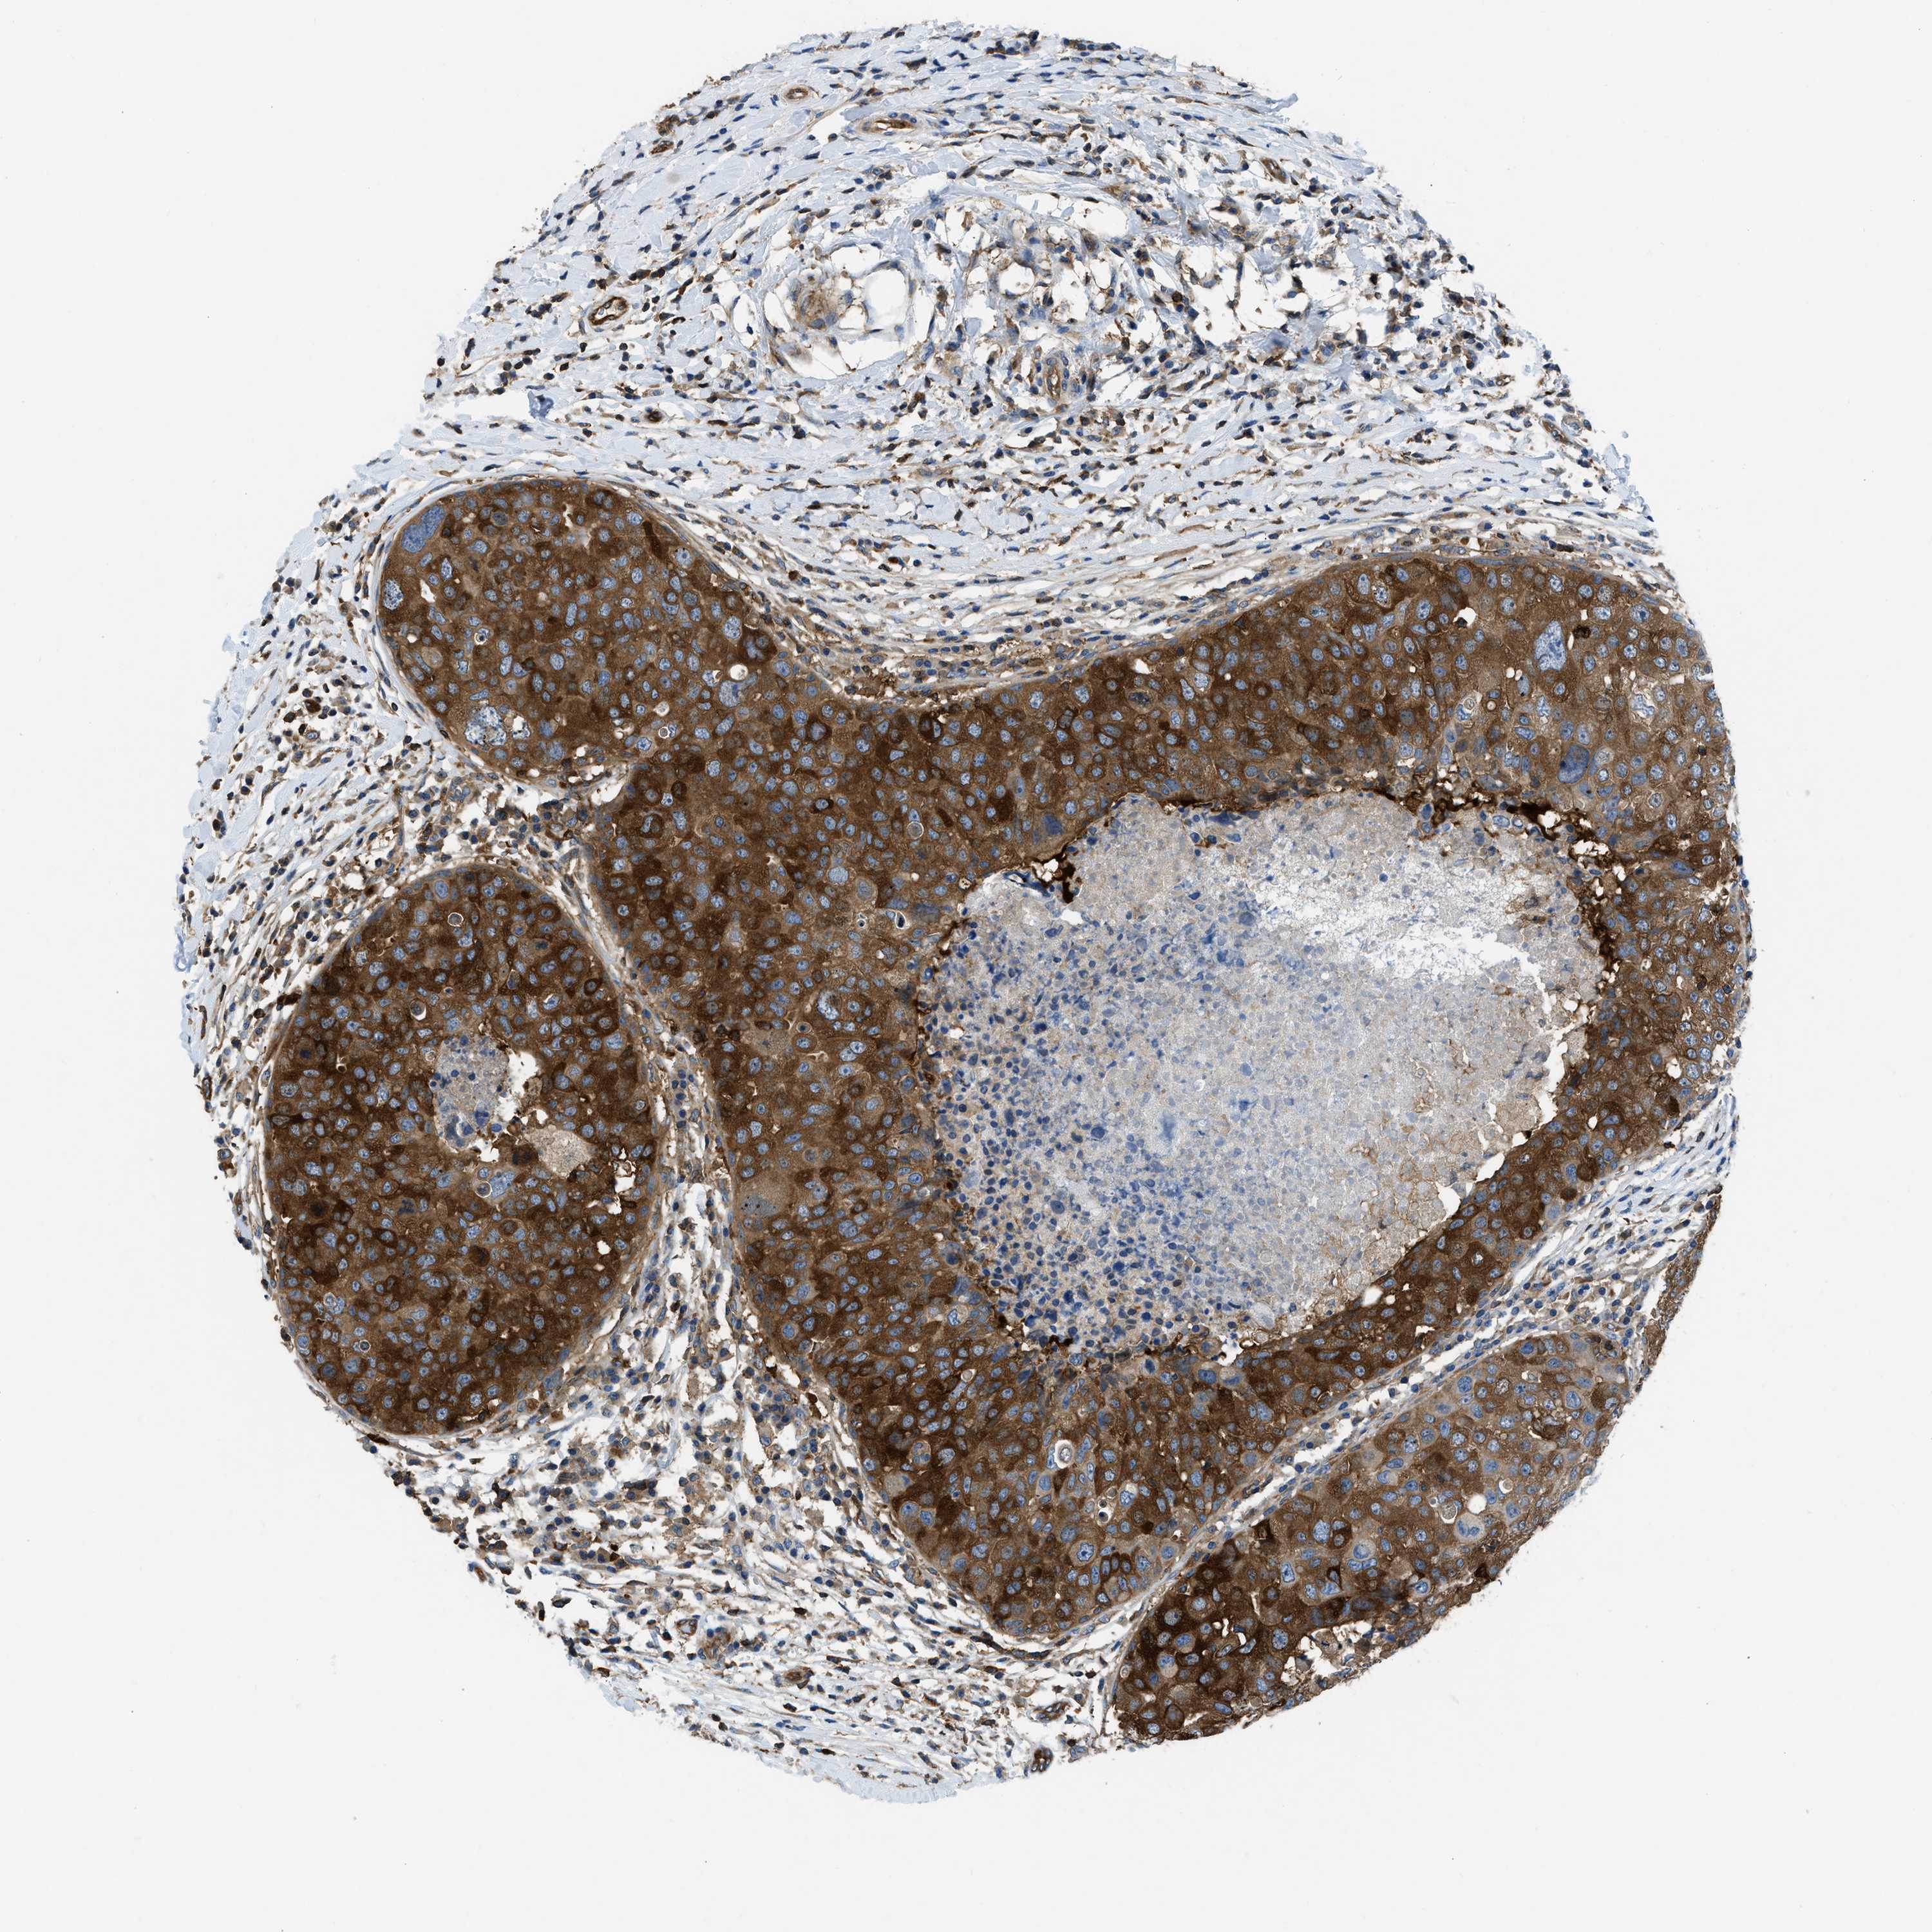

CANCER BREAST CANCER Show tissue menu

BRCA TCGA BRCA VALIDATION PROTEIN EXPRESSION